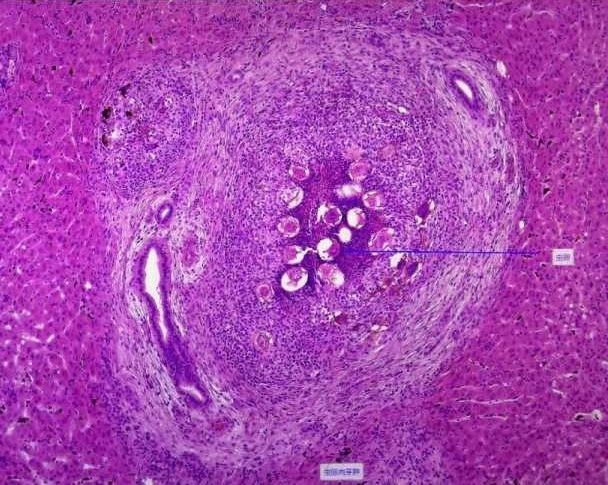

裂体吸虫